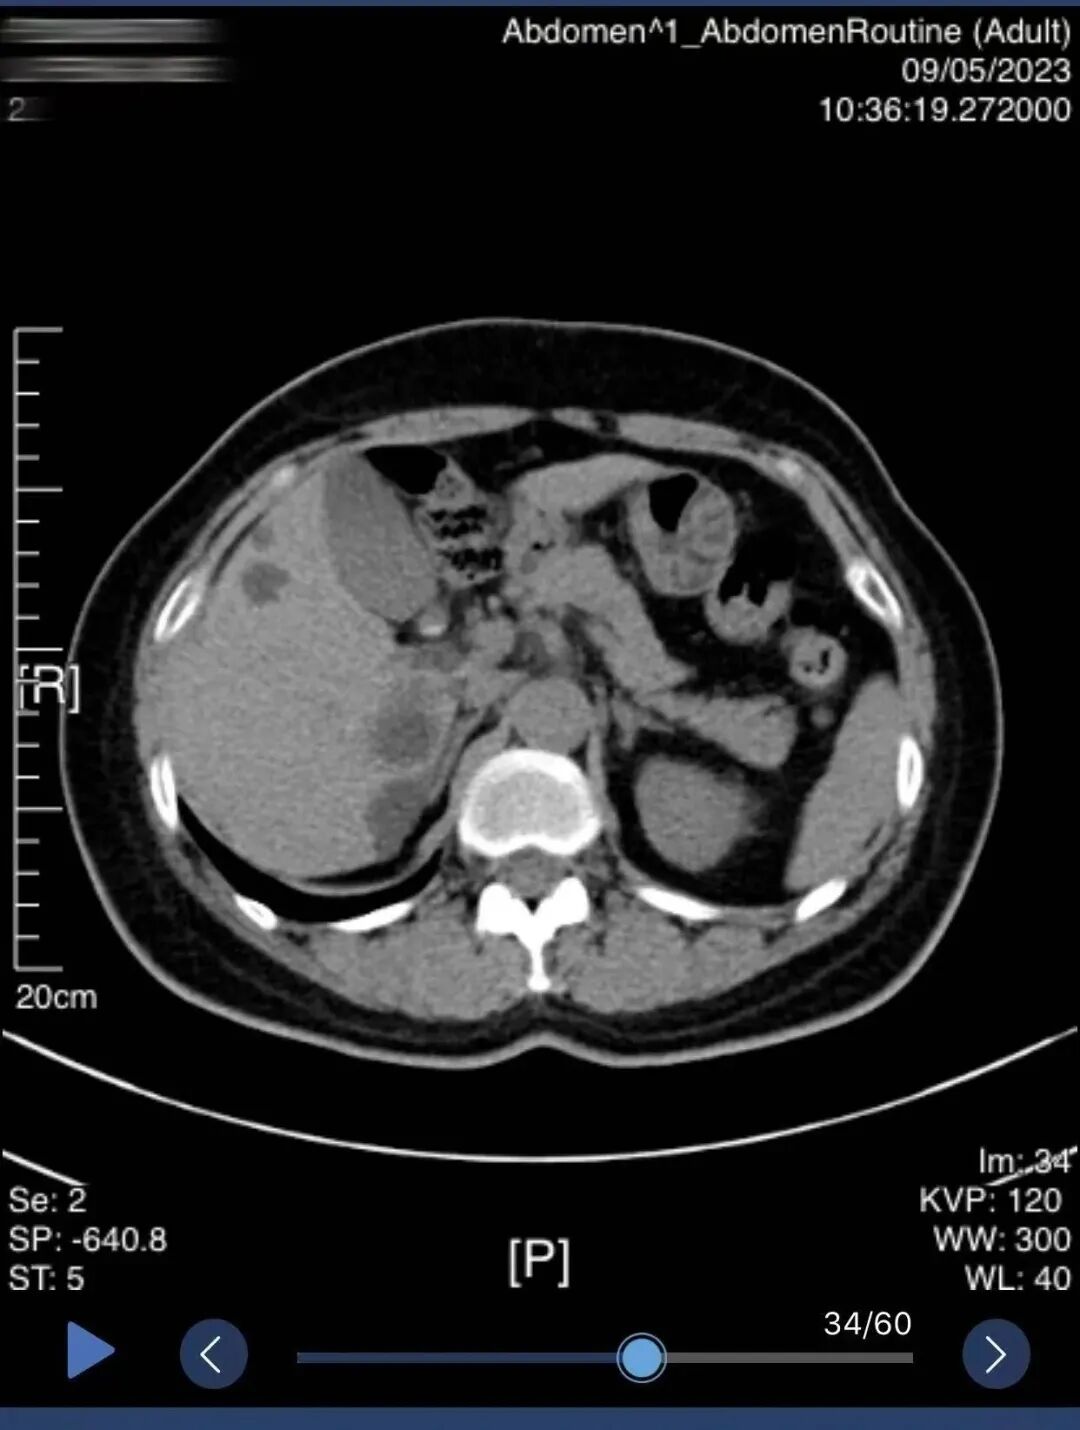

北京常驻专家脾胃病科主任王秋明,详细询问患者既往病史、现症状,进行望闻问切,完善相关辅助检查后,腹部CT示点状高密度结石,巨大结石未显影。王主任告诉李阿姨,这种X线阴性结石以胆固醇成分为主,具有溶石指征,可暂缓手术。经与李阿姨充分沟通后,同意诊疗方案。